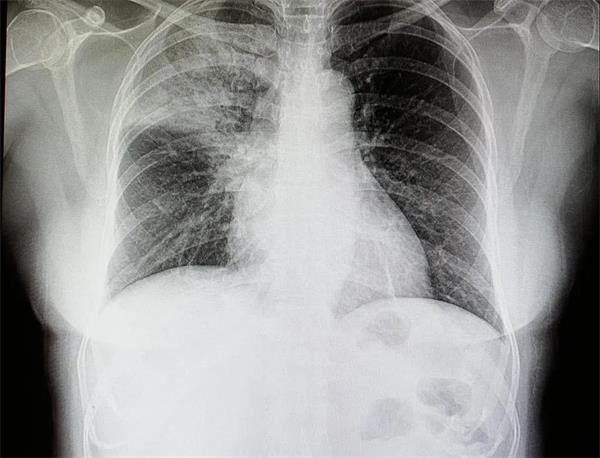

▲ 图为患有潜在大叶性肺炎患者的胸部X光片

同时,这篇期刊文章还讨论了对这项技术的深入考量:“此前的临床研究表明,COVID-19肺炎在胸部造影学层面上显示出一定特征,但仍有高达56%的有症状患者、特别是在其早期患病阶段,很可能拥有看似正常的胸部X光片。因此,医学造影不技术不适合用于「排除」疾病。此外,对COVID-19病患进行的成像实现发现,大部分结果都具有非特异性表现,即与其他病毒性肺炎存在特征重叠。因此,胸部成像不应用作COVID-19的诊断工具,但仍可在早期识别潜在病患方面发挥积极作用,包括帮助对病患进行分类以及感染控制。”

这篇报道还警告称,“当然,也有一部分COVID-19病患不会表现出任何症状,包括在胸部X光片中不存在任何异常。在病毒感染的早期阶段,很多患者的肺部未出现任何异常。”在这类情况下,这一AI放射学工具可能发挥不了多大作用。